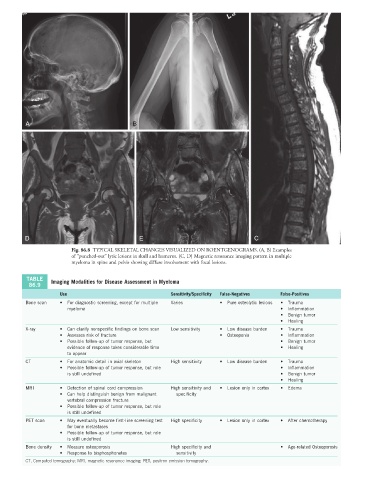

Fig. 86.8 TYPICAL SKELETAL CHANGES VISUALIZED ON ROENTGENOGRAMS. (A, B) Examples

of “punched-out” lytic lesions in skull and humerus. (C, D) Magnetic resonance imaging pattern in multiple

myeloma in spine and pelvis showing diffuse involvement with focal lesions.

TABLE Imaging Modalities for Disease Assessment in Myeloma

86.9

Use Sensitivity/Specificity False-Negatives False-Positives

Bone scan • For diagnostic screening, except for multiple Varies • Pure osteolytic lesions • Trauma

myeloma • Inflammation

• Benign tumor

• Healing

X-ray • Can clarify nonspecific findings on bone scan Low sensitivity • Low disease burden • Trauma

• Assesses risk of fracture • Osteopenia • Inflammation

• Possible follow-up of tumor response, but • Benign tumor

evidence of response takes considerable time • Healing

to appear

CT • For anatomic detail in axial skeleton High sensitivity • Low disease burden • Trauma

• Possible follow-up of tumor response, but role • Inflammation

is still undefined • Benign tumor

MRI • Detection of spinal cord compression High sensitivity and • Lesion only in cortex • Edema

• Can help distinguish benign from malignant specificity

vertebral compression fracture

• Possible follow-up of tumor response, but role

is still undefined

PET scan • May eventually become first-line screening test High specificity • Lesion only in cortex • After chemotherapy

for bone metastases

Bone density • Measure osteoporosis High specificity and • Age-related Osteoporosis

• Response to bisphosphonates sensitivity

CT, Computed tomography; MRI, magnetic resonance imaging; PET, positron emission tomography.